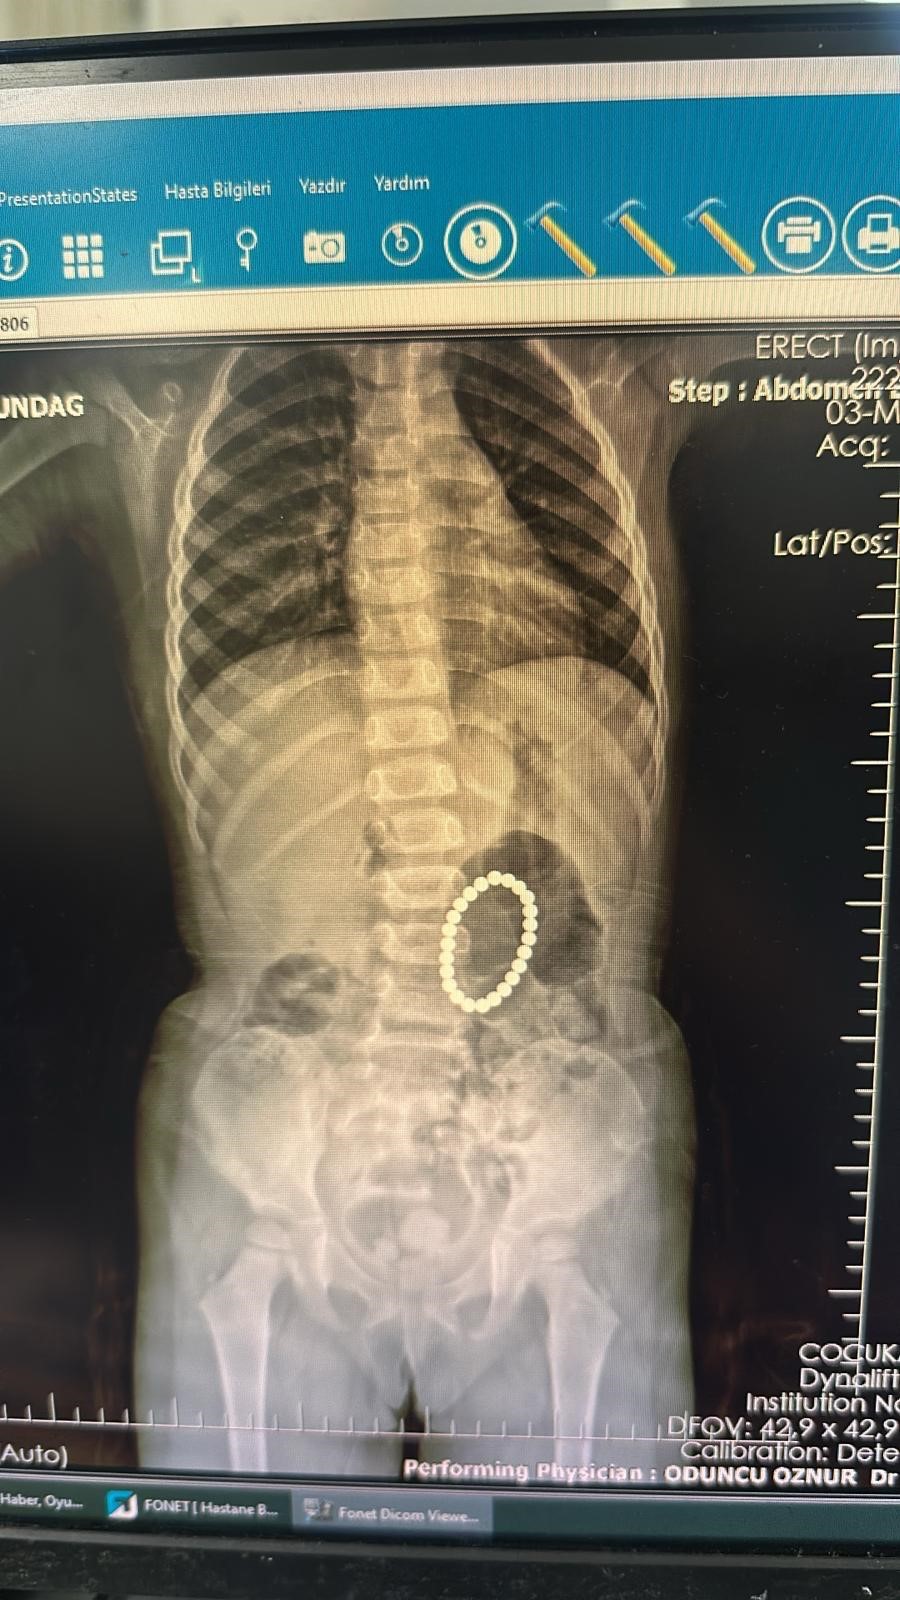

Şırnak'ta yoğun karın ağrısı şikayeti ile önce Cizre Devlet Hastanesine ardından da Şırnak Devlet Hastanesine götürdükleri kızları Rumeysa Altundağ (4), Batman Eğitim ve Araştırma Hastanesine sevk edildi. Batman'a getirilen Rumeysa Altundağ'ı muayene eden Batman Eğitim ve Araştırma Hastanesi Çocuk Cerrahisi Doktor Selim Özkaya daha sonra hastaya endoskopi yaptı. Yapılan endoskopide küçük kızın bağırsaklarında ve midesinde bileklik şeklinde yabancı cisimlerin olduğu belirlendi. Ameliyata alınan Rumeysa Altundağ'ın bağırsakları ve midesinden 24 adet renkli oyuncak mıknatıs çıkartıldı.

İlk defa böyle bir vaka ile denk geldiklerini belirten Doktor Selim Özkaya, yapılan ameliyatın ardından başarılı bir şekilde tamamlandığını söyledi. Mıknatısların bağırsaklarda kısmen delinmelere neden olduğunu belirten Dr. Özkaya, "Hastamız 4 yaşında kız hasta. Yoğun karın ağrısı nedeniyle Şırnak'ta devlet hastanemize başvurmuş, yapılan tetkiklerinde yabancı cisim yuttuğu tespit edilmiş. Bunun üzerine endoskopi yapılmak üzere hastanemize Gastroentoloji bölümüne sevk edildi. Endoskopi sırasında tespit edilen yabancı cisimlerin renkli mıknatıslar olduğu, yarısının da midede gözükmediği görüldü. Hastamız 24 tane renkli küçük mıknatıs yutmuştu. Endoskopi işleminden sonra hastamıza operasyon planladık. Yaptığımız ameliyatta da farklı zamanda yutulan mıknatısların yarısının midede yarısının bağırsaklarda olduğu ve bunların birbirine yapışarak bağırsak kısımlarında delinmelere neden olduğu görüldü. Bu kısımları onardık. Hastamız ameliyattan sonra beslenmesine de başladı, herhangi bir sıkıntısı yok, taburcu etmeyi planlıyoruz" dedi.

Çıkartılan mıknatısları yaklaşık 1 yıl önce yutulduğuna dikkati çeken Dr Özkaya, "Bu mıknatısların bir yıl gibi bir süredir yuttuğunu düşünüyoruz. Çünkü bu mıknatısların artık renkleri de değişmiş durumda ve paslanmış durumda. O yüzden de bir yıldır ara ara karın ağrısı çekiyormuş. Bunlar renkli renkli ve kuvvetli mıknatıslar" ifadelerini kullandı.